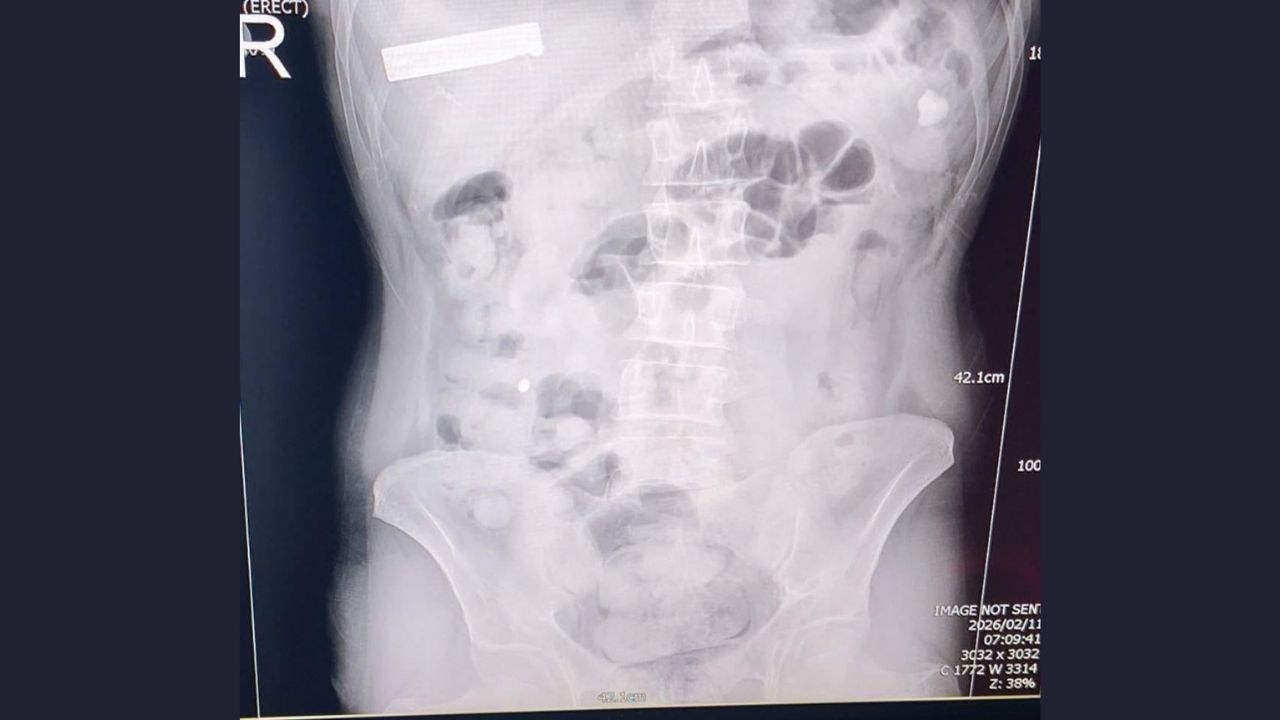

Uşak Emniyet Müdürlüğü Narkotik Suçlarla Mücadele Şube Müdürlüğü ile İstihbarat Şube Müdürlüğü ekiplerinin ortaklaşa çalışması sonucu yürütülen çalışmalar ve takipler neticesinde il merkezinde yakalanan İran uyruklu 2 şüpheli şahsın hastanede yaptırılan kontrolleri ve çekilen röntgen filmleri neticesinde mide ve bağırsaklarında çok sayıda yasaklı madde içeren kapsül bulunduğu tespit edildi.

Hastanede kontrollü bir şekilde gözetim altında tutulan şüphelilerden tıbbi müdahaleler neticesinde toplam;

93 parça halinde, 1 kilo 70 gram Metamfetamin ele geçirildi.